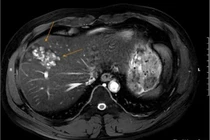

Khi tiếp nhận, bệnh nhân được thăm khám lâm sàng, làm xét nghiệm máu và các kỹ thuật chẩn đoán hình ảnh. Kết quả ghi nhận dương tính với sán lá gan lớn và giun đũa chó mèo; đồng thời phát hiện ổ áp xe gan kích thước xấp xỉ 5 cm, kèm theo tăng chỉ số viêm và tăng bạch cầu ái toan.

Theo BS Hương: “Ổ áp xe gan khá lớn. Nếu bệnh nhân đến muộn có thể dẫn đến vỡ ổ áp xe và nhiễm khuẩn huyết”.

Sau khi đánh giá toàn diện, bệnh nhân được chỉ định phác đồ điều trị gồm chọc hút ổ áp xe, thuốc đặc hiệu diệt ký sinh trùng, kháng sinh kiểm soát nhiễm trùng và theo dõi sát bạch cầu ái toan, men gan cùng các chỉ số viêm.

Trong quá trình điều trị nội trú và theo dõi ngoại trú bạch cầu ái toan đã trở về mức bình thường, ổ áp xe gan thu nhỏ, không còn dịch mủ, tình trạng sốt và đau hạ sườn phải giảm rõ rệt, tình trạng ngứa gần như biến mất. Hiện tại sức khỏe bệnh nhân đã ổn định.